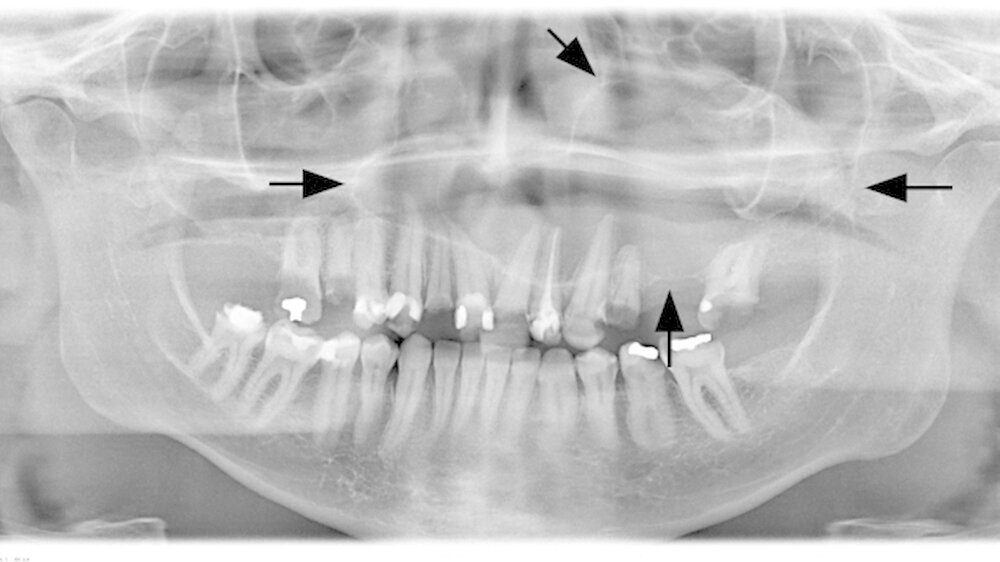

Der intraorale Zahnstatus beschreibt einen insgesamt sanierungsbedürftigen Zustand mit diversen nicht erhaltungswürdigen Zähnen im Unter- und Oberkiefer. Der Oberkiefer zeigte klinisch im zweiten Quadranten eine ausgeprägte palatinale Schwellung (Abbildung 2). Die Panoramaschichtaufnahme bestätigte den klinischen Verdacht auf eine ausgedehnte osteolytische Raumforderung im Oberkiefer. Diese erstreckte sich vom linken Oberkiefer die Mittellinie überschreitend, die gesamte linke Kieferhöhle einnehmend bis zur Regio 14 gehend (Abbildung 3). Durch den Hauszahnarzt konnte ein sechs Jahre zuvor erstellter Zahnfilm zur weiteren Diagnostik hinzugezogen werden.

Bereits damals wurde vom Hauszahnarzt eine Entfernung der noch umschriebenen Raumforderung dringend empfohlen. Der Zahnfilm zeigte ein zystisches Geschehen in der Regio 24 und 25 (Abbildung 4). Zur aktuellen weiteren präoperativen Diagnostik wurde eine Computertomografie angefertigt. In den coronalen Schnitten ist die die Mittellinien überschreitende Raumforderung bis zum knöchernen Nasenboden unter Einbezug der linken Kieferhöhle deutlich zu sehen (Abbildung 5a). Man erkennt insbesondere in den sagittalen Schnitten, dass die Raumforderung über zwei Drittel der linken Kieferhöhle beansprucht (Abbildung 5b).